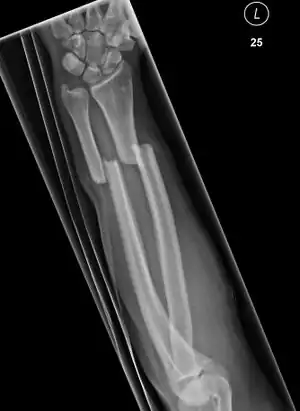

| Midshaft fracture of the radius and ulna | |

A forearm fracture refers to one or more breaks of the bones in the forearm; a radius fracture or ulna fracture, or more commonly both.[3][6] The bones can break in several places; near the wrist, in the middle or near the elbow.[7] When both bones break, the breaks occur at around the same level.[6] The fractures can be closed, with skin intact, or open, where there is accompanying overlying wound, and are often associated with wrist or elbow joint damage such as dislocation or displacement.[4][1]